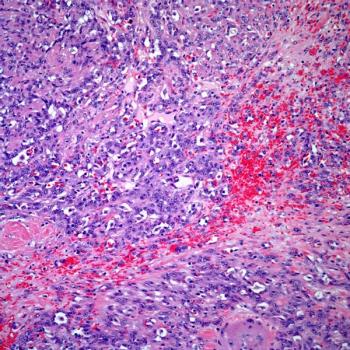

Bladder Cancer